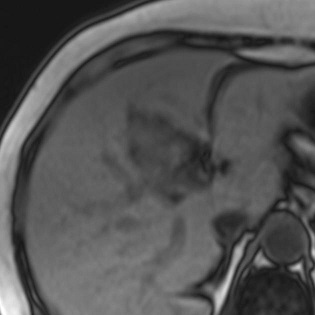

Image IRM de steatose fu foie

: Image de

hyperintense sur T1 et hypointense surT2 . L'infiltration graisseuse du foie provoque une diminution de

l'attenuation du parenchyme du foie . Sur le foie normale le

signal du parenchyme hepatique est similaire sur toutes les

images "in phase " et "opposed phase " . Dans steatose du

foie le signal du foie est hyperintense relative avec la rate (

T1 in phase ) et a opposed-phase , par la chute de

signal , image du foie est hypointensite ,

Steatose du foie : en phase .

Image IRM du foie |

|

Steatose du foie : Op de phase . |